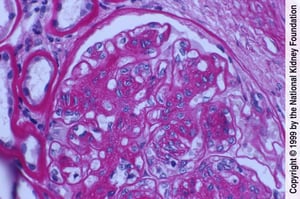

Sono caratteristiche le lesioni della glomerulosclerosi intercapillare diffusa o nodulare; aree di nefrosclerosi nodulare possono essere attribuite a lesioni di Kimmelstiel-Wilson. Vi è una marcata ialinosi, così come un'arteriosclerosi delle arteriole afferenti ed efferenti; possono essere presenti fibrosi interstiziale e atrofia tubulare. L'espansione della matrice mesangiale sembra essere correlata all'evoluzione verso l'insufficienza renale terminale (1).

La proliferazione delle cellule mesangiali e l'espansione della matrice con danno endoteliale si manifestano qui come ispessimento delle membrane basali glomerulari senza evidenti depositi di immunocomplessi (colorazione con acido periodico di Schiff, ×400).

Imagine fornita da Agnes Fogo, MD, and the American Journal of Kidney Diseases' Atlas of Renal Pathology (vedi www.ajkd.org).